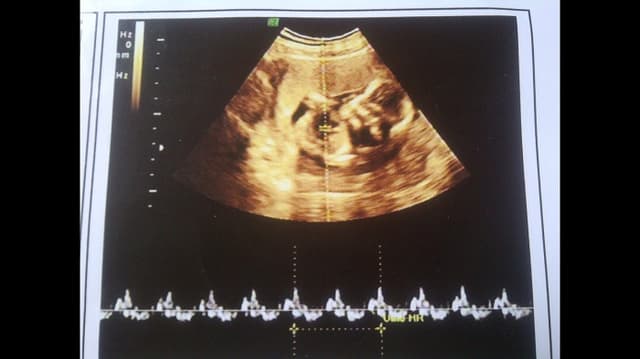

Nhịp tim thai 7 tuần là bao nhiêu?những điều cần biết

Rất nhiều mẹ thắc mắc thai 7 tuần nhịp tim bao nhiêu. Hãy cùng tìm hiểu một số thông tin về nhịp tim thai nhi 7 tuần tuổi trong bài viết sau đây. 1. Nhịp tim thai 7 tuần là bao nhiêu? Theo các bác sĩ tại bệnh viện ĐKQT Thu Cúc, ngay từ ngày […]